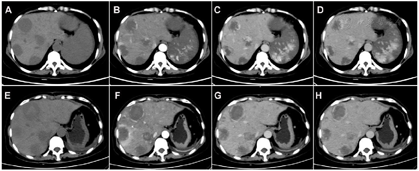

①腹部增强CT:肝脏多发低密度影,增强呈外周向内扩展的渐进性强化;脾脏明显肿大,增强呈渐进性的不均匀强化(图1,图2);诊断意见:考虑肝、脾血管源性肿瘤(血管瘤?血管肉瘤?)。

②18F-FDG PET/CT:脾脏明显增大,约23.1 cm×12.4 cm×24.5 cm,密度弥漫性减低,平均CT值约39 Hu,其内见多发条片状更低密度影,CT值约31 Hu,脾脏18F-FDG代谢不均匀性轻度增高,SUVmax=5.4;肝内多发类圆形低密度影,形态规则,边缘光整,最大者直径4.4 cm,密度均匀,平均CT值约42 Hu,病灶18F-FDG摄取均匀,与肝本底无差异,SUVmax=3.3(图1);诊断意见:巨脾伴18F-FDG代谢不均匀轻度增高,倾向恶性病变(原发);肝内多发低密度灶未见18F-FDG代谢异常,倾向良性病变(血管瘤)。